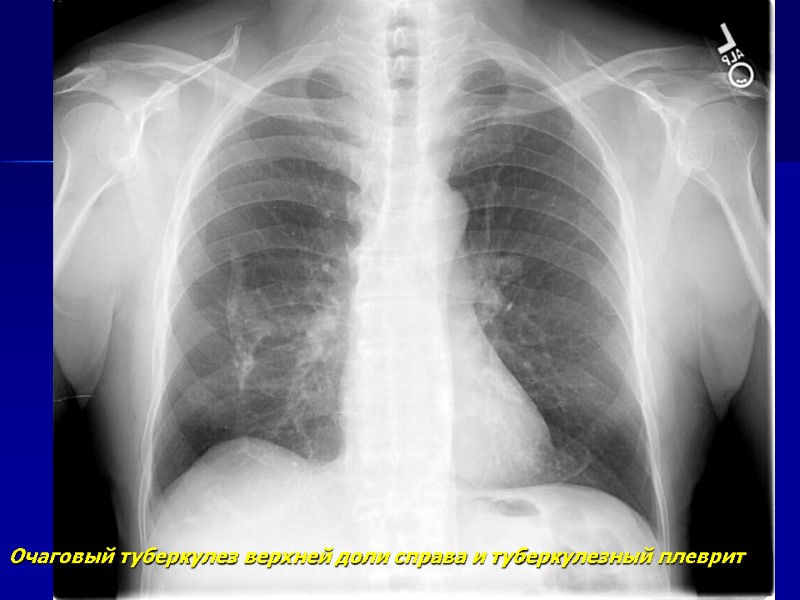

Очаговый туберкулез верхней доли справа и туберкулезный плеврит